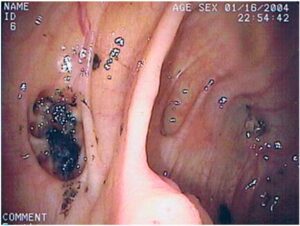

- Blood in the Sool (Uncommon but Song Russian is Serious)

Diverticulitis does not usually result in bleeding, but diverticular bleeding may take place.

You may see:

- Bright red blood on the toilet paper.

- Streaks of blood on the stool

- Bloody mucus

In case you observe black, tar-like stool, this can be an indication of increased bleeding in the intestines and should be taken to the doctor immediately.